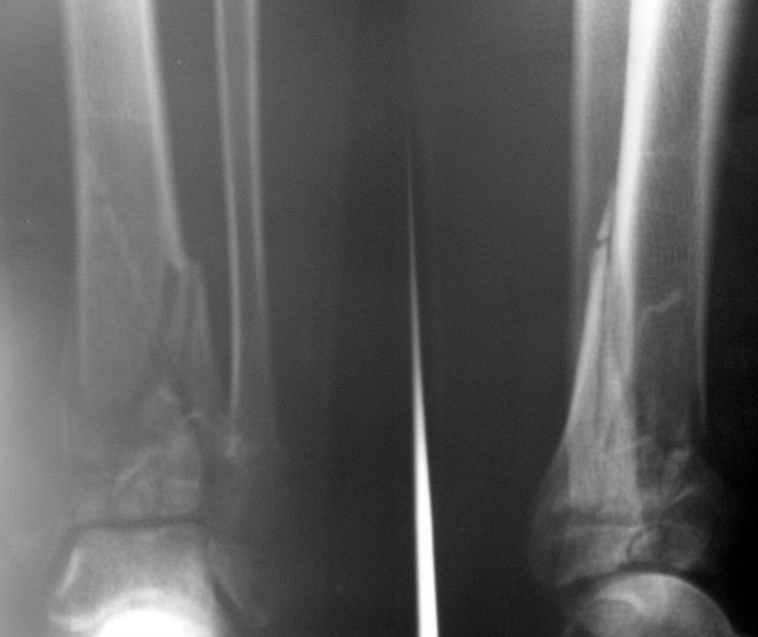

Перелом пилона 6-недельной давности

1,5 месяца назад при падении со скалы получил перелом пилона, лечился в районной больнице консервативно (циркулярная гипсовая повязка до средней 1/3 бедра). К нам попал только сегодня, сделали снимки и возник вопрос - делать ли что-то хирургически или уже пойти только на восстановительное лечение (продолжить иммобилизацию еще на 2-4 недели, потом разработка движений и т.п.)? Снимки прилагаю.